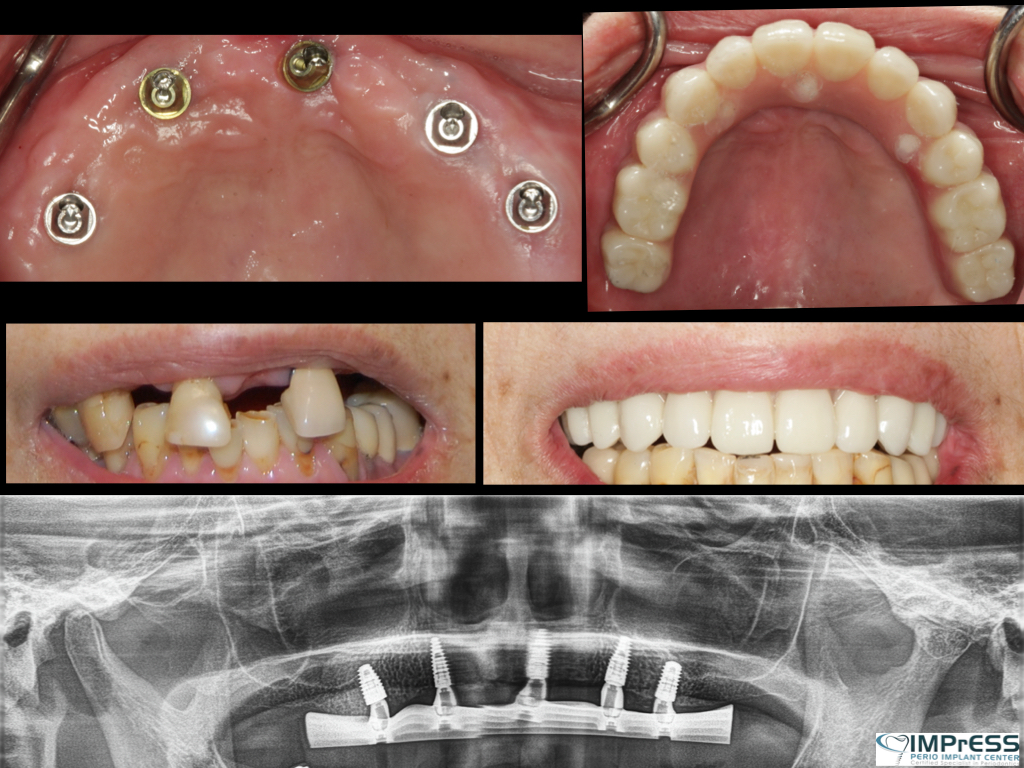

Full Mouth Reconstruction with Fixed Implant Bridge – All on X

All on X implant Full Mouth Implant Reconstruction All on 4 Implants IMPrESS Perio Implant Center Vancouver Burnaby Periodontist Prosthodontist Implant Specialist Dr. Noroozi Periodontist Implant Specialist